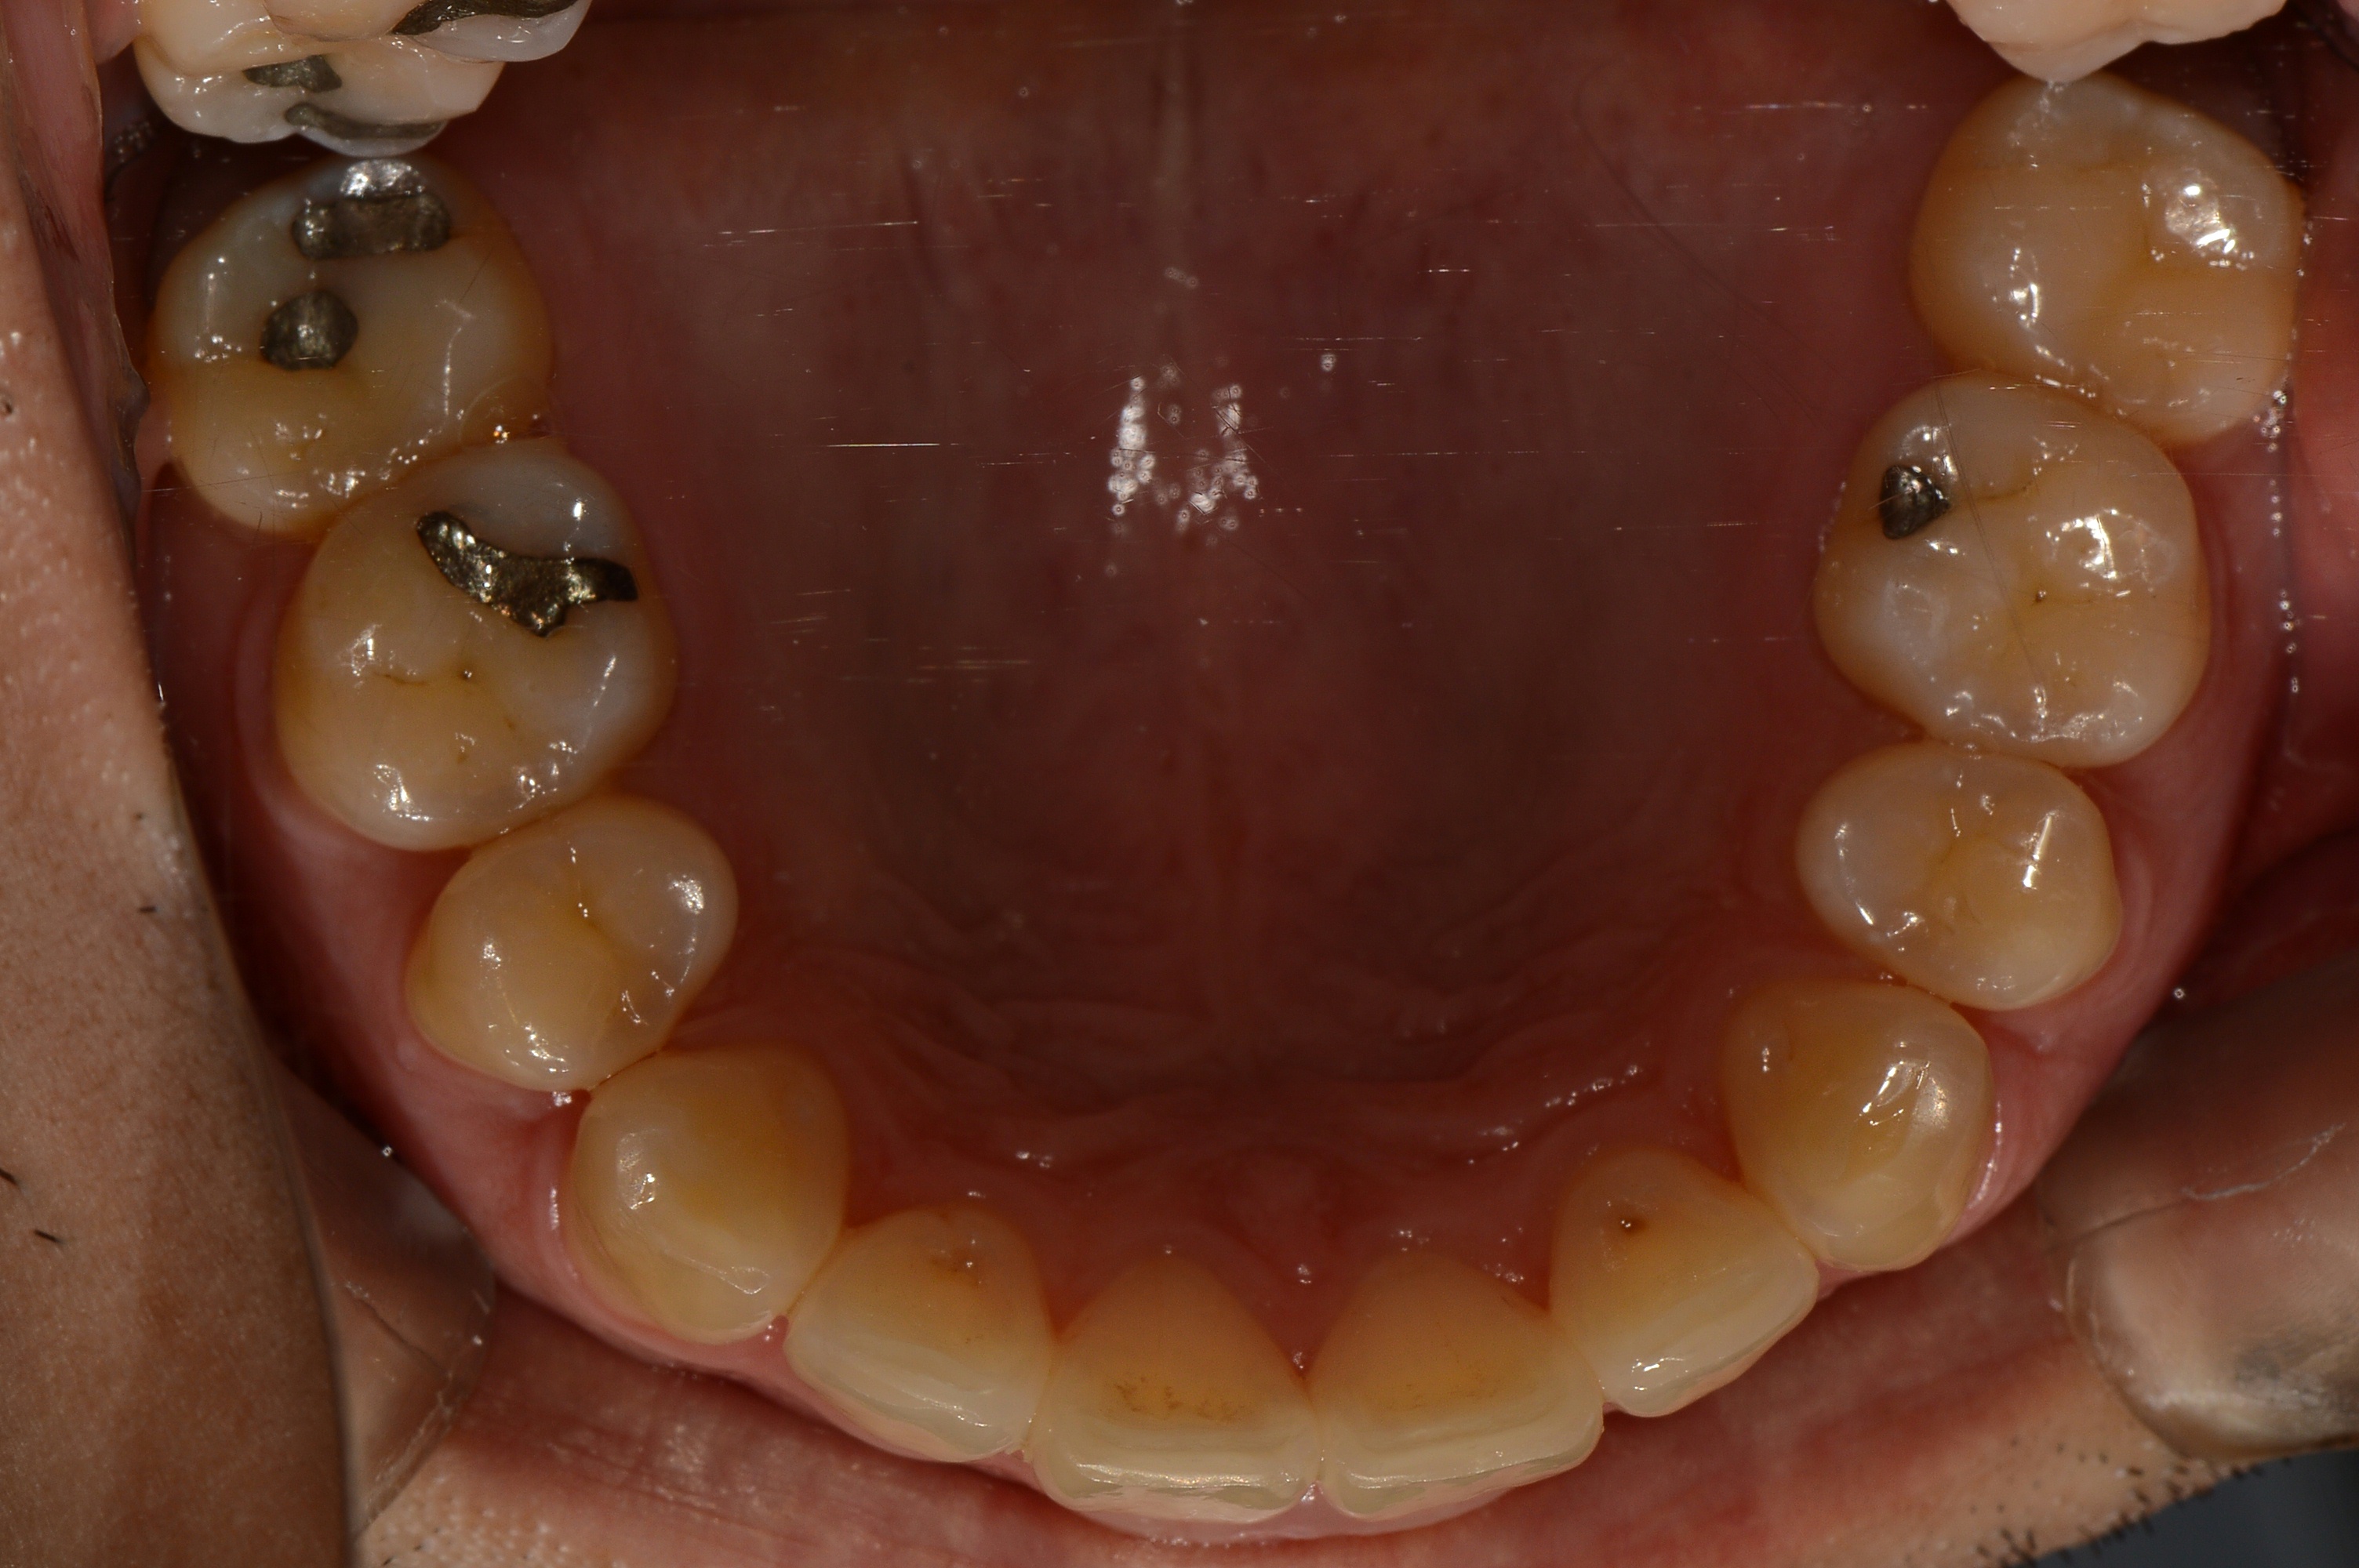

치료 전 사진입니다.